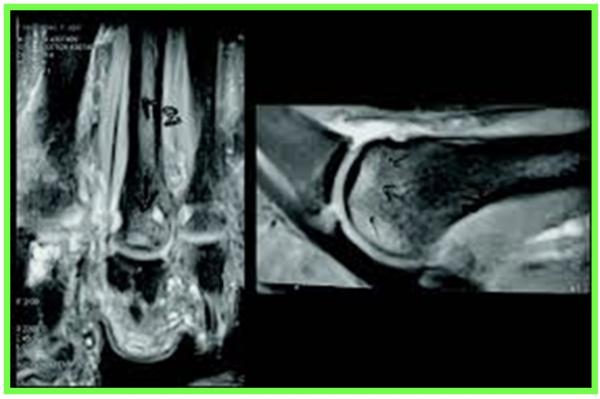

SYNDROME DU 2 EME RAYON :

Le Syndrome du 2ème rayon est un syndrome douloureux dû à une surcharge mécanique sur l’articulation métatarso-phalangienne du 2éme orteil.

L’évolution se fera par la suite vers une déformation progressive du 2éme orteil

En fonction de l’importance de la lésion de la plaque plantaire (fissure simple ou complexe, déchirure), cela crée une déviation de l’orteil, perte d’appui, chevauchement d’orteils, apparition d’une « griffe », dislocation articulaire métatarso-phalangienne.

RADIOGRAPHIE DU PIED EN CHARGE F + P, ECHOGRAPHIE

IRM : Bursite , rupture de la plaque plantaire